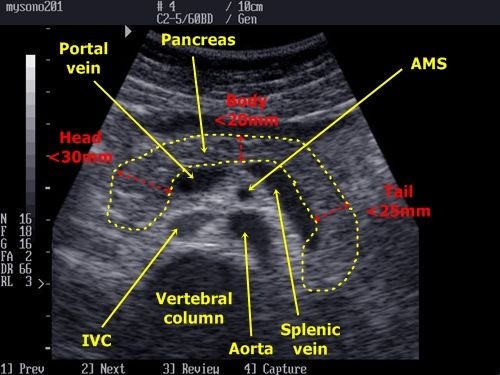

Whether you or someone y. The pancreas is located behind the stomach, so having pancreatic cancer doesn't involve a palpable mass that you can feel. Hearing the doctor tell you that you've got cancer is undoubtedly one of the worst things you may experience. Of course, your specialist is the main person whose advice you should follow but it doesn't do anyone harm. The pancreas is an organ that releases enzymes involved with digestion, and hormones to regular blood sugar levels.